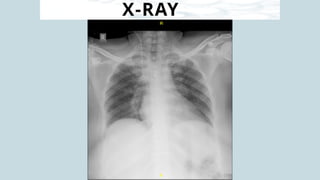

X-RAY